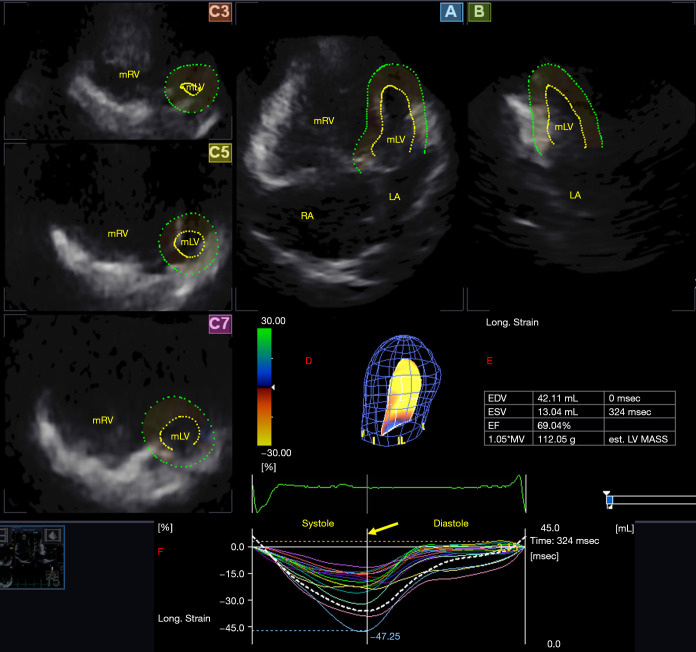

Background: Dextro-transposition of the great arteries (dTGA) stands out as a prevalent cyanotic congenital heart defect (CHD), characterized by an intricate reversal in the arrangement of the major arteries. In the past, several surgical procedures have been used to treat dTGA, including the atrial switch. Although the method is no longer used, survivors of the procedure still living among us. Recent advancements in cardiovascular imaging have led to the emergence of several novel echocardiographic techniques, notably three-dimensional (3D) and/or speckle-tracking echocardiography (STE). The present study aimed to employ 3DSTE to determine morphologic left ventricle (mLV) strain parameters in adults with dTGA who underwent Senning or Mustard procedure at infancy. Furthermore, it was also aimed to assess whether the type of correction procedure had any impact on mLV deformation parameters.

Methods: Eleven dTGA patients, with a mean age of 28.8±8.5 years (6 males, 6 Senning- and 5 Mustard-operated patients) were enrolled. They were compared to 34 healthy controls matched for age and gender (age: 35.7±12.8 years, 21 males). All subjects underwent complete two-dimensional (2D) Doppler echocardiography with 3DSTE data acquisition as per recent guidelines.

Results: Comparing all dTGA patients to the control group no mean segmental or global mLV strains showed significant differences, however out of the regional strains, midventricular mLV longitudinal strain was significantly better (higher) in dTGA compared to the healthy group (-16.8%±7.4% vs. -13.3%±2.5%, P<0.05). The Mustard-operated patients showed significantly worse (lower) global mLV circumferential strain compared to that of controls (-22.1%±12.4% vs. -28.9%±4.7%, P=0.05). Out of the regional strains the Mustard procedure group had a significantly worse (lower) apical mLV circumferential strain (-24.8%±11.9% vs. -35.6%±9.0%, P=0.05), better (higher) midventricular mLV longitudinal strain (-20.1%±9.2% vs. -13.3%±2.5%, P=0.04) and a worse (lower) apical mLV area strain (-36.3%±17.0% vs. -48.8%±9.7%, P=0.03).